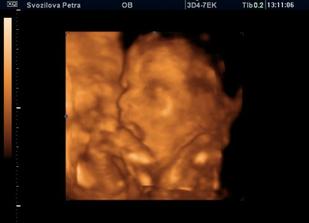

Nase miminko